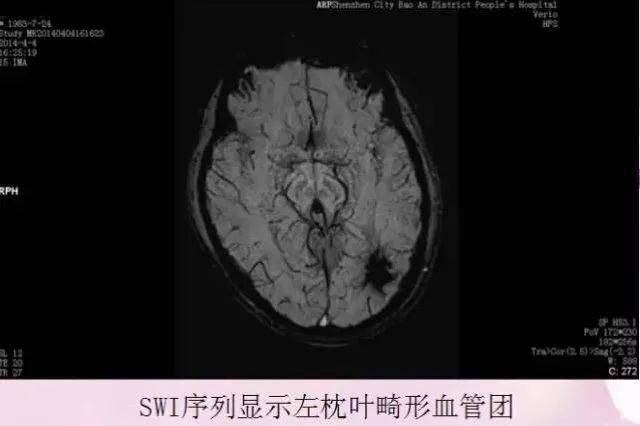

磁敏感成像技术(SWI)可以检测出颅脑微小出血、血管畸形、肿瘤的引流静脉、铁质异常沉积等。